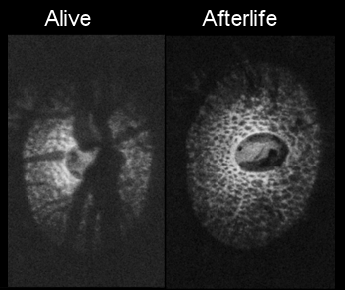

• Seeing the hidden lamina; Effects of exsanguination on the optic nerve head

• H Tran, J Wallace, Z Zhu, KA Lucy, AP Voorhees, SE Schmitt, RA Bilonick, JS Schuman, MA Smith, G Wollstein, and IA Sigal

• Investigative Ophthalmology and Visual Science, 59, 2564-2575, May 2018.